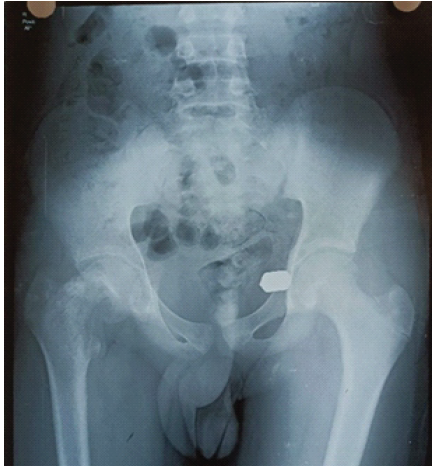

Hip disorders in the paediatric population (patients <16 years) represent a varied collection of conditions ranging from traumatic, developmental, infectious, neoplastic, and metabolic causes [1]. These pathologies, if not promptly diagnosed and treated, frequently result in long-term morbidity, including permanent deformities, chronic pain, gait abnormalities, and compromised quality of life in adulthood [1,2]. The unique developmental anatomy of the pediatric hip, characterized by the presence of a vulnerable physeal plate and changing vascular patterns, contributes to its susceptibility to specific age-related diseases [3]. Common non-traumatic paediatric hip disorders include developmental dysplasia of the hip (DDH) (Fig. 1), Legg-Calvé-Perthes disease (Perthes’) (Fig. 2 and 3), slipped capital femoral epiphysis (SCFE) (Fig. 4), and infective conditions such as septic arthritis (Fig. 5) and tubercular arthritis [3].

Figure 1: Image showing the small dysplastic femur head outside the shallow acetabulum cavity in upper outer quadrant.